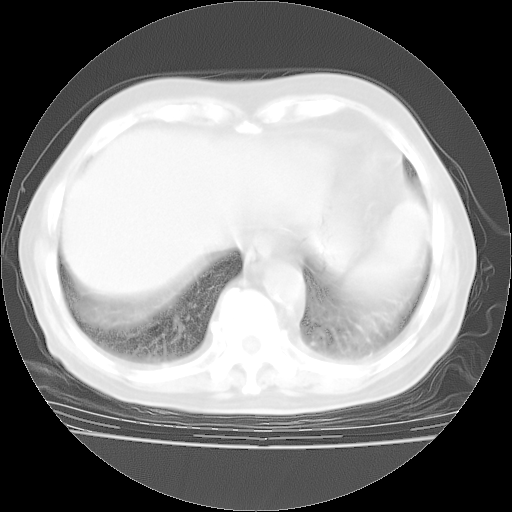

4月28日肺部CT——再次出现类似去年5月9日——透光度降低,“间质性”改变。

个人阅读4.14日肺部CT平扫:纵隔窗无异常,但肺窗示:双下肺内、后基底段有片絮状侵润影,部位以后基底段为著,以间质改变为主,呈急性肺泡炎征像,和首次住院影像学有相似之处。仅是个人读片,明日请相关专家再读片哈。其它建议同上。

1、108#的是4月14日的胸部CT(发此贴时还没看着28日的CT)。14日的胸部CT其实已经出现改变(如108#所述),个人认为28日的胸部CT除纵膈窗疑似有双侧胸膜增厚或少量胸积液(可行胸部B超明确)外,与4月14日对照病变有所加重;2、已经给予“异烟肼、利福平、乙胺丁醇”抗痨治疗?如果是,甲强龙80mg可缓慢减量;如果环磷酰胺已停用,暂不使用;3、中性粒细胞92%,明显升高,目前体温情况?注意合并细菌感染可能,使用左氧氟沙星情况下,是否联用B-内酰胺类抗菌药物?另外是查免疫全套非风湿全套。

今请临免主任会诊后认为:4月14日胸部CT已有双下肺间质性改变。患者病情复发多系激素减量过快不正规所致。目前甲强龙80mg/日,一周后酌情开始减量,不易过快。环磷酰胺若已停用,暂不使用。他同意目前抗菌药物使用,但应考虑是否加用B-内酰胺类抗菌药物(中性细胞明显增高);2、结核复发目前依据不足;3、若免疫全套各项指标正常,考虑多系特发性肺间质炎可能大。4、加强支持,并注意保护胃黏膜。